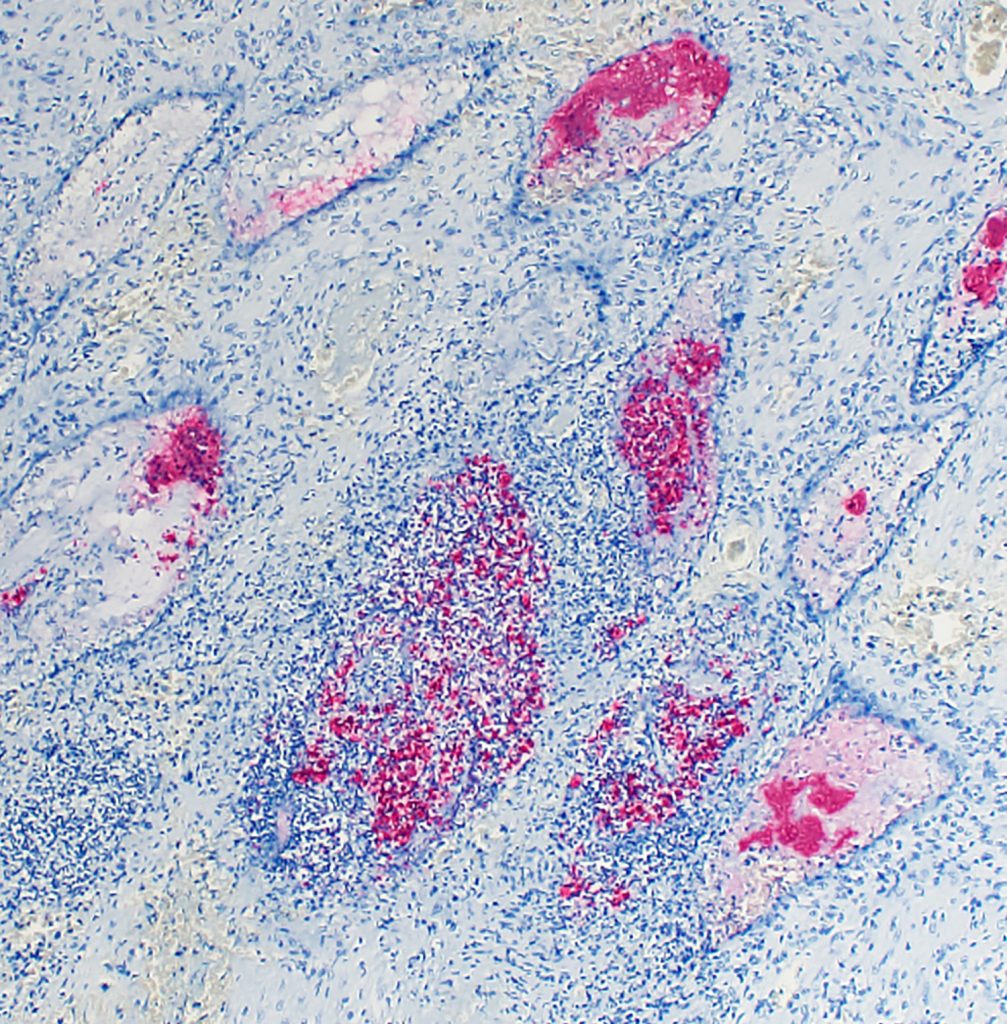

The BSL-3 facility allows faculty and technicians to safely study and diagnose infectious diseases. In particular, BSL-3 labs are approved for study and diagnosis of select agents, or federally regulated microbes. To prevent the spread of these diseases, security and procedures in the facility are regulated by the CDC and FBI.

At the WSVL, the BSL-3 is used for diagnoses, necropsies, and vaccination research related to diseases like HPAI and brucellosis. In this highly secure environment, WSVL staff also run diagnostics for potential cases of Q-fever, plague, tularemia, anthrax, and other infectious diseases transmitted by wild and domestic animals. In 2021, COVID-19 testing was conducted in the facility.

Enhanced biosafety facilities provide an opportunity not only to diagnose diseases like HPAI, but also to conduct follow-up research. These investigations can help scientists better understand disease transmission and pathogenesis, and even develop vaccines.

“The BSL-3 labs at WSVL provide the ideal environment to explore these questions following high biosafety and biosecurity standards,” Brower notes. “Our lab’s ability to study these infectious agents in such a setting is not only critical for understanding how a virus like HPAI behaves but also for developing more effective prevention and control strategies to protect both human and animal health.”